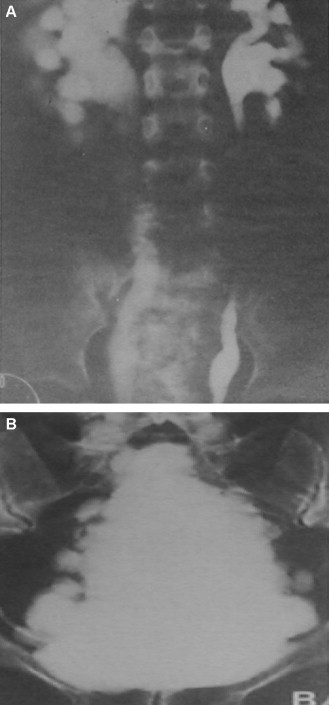

Quel est cet examen? Que voit-on?

Urétrocystographie rétrograde et mictionnelle = vessie de lutte car aspect en arbre de Noël